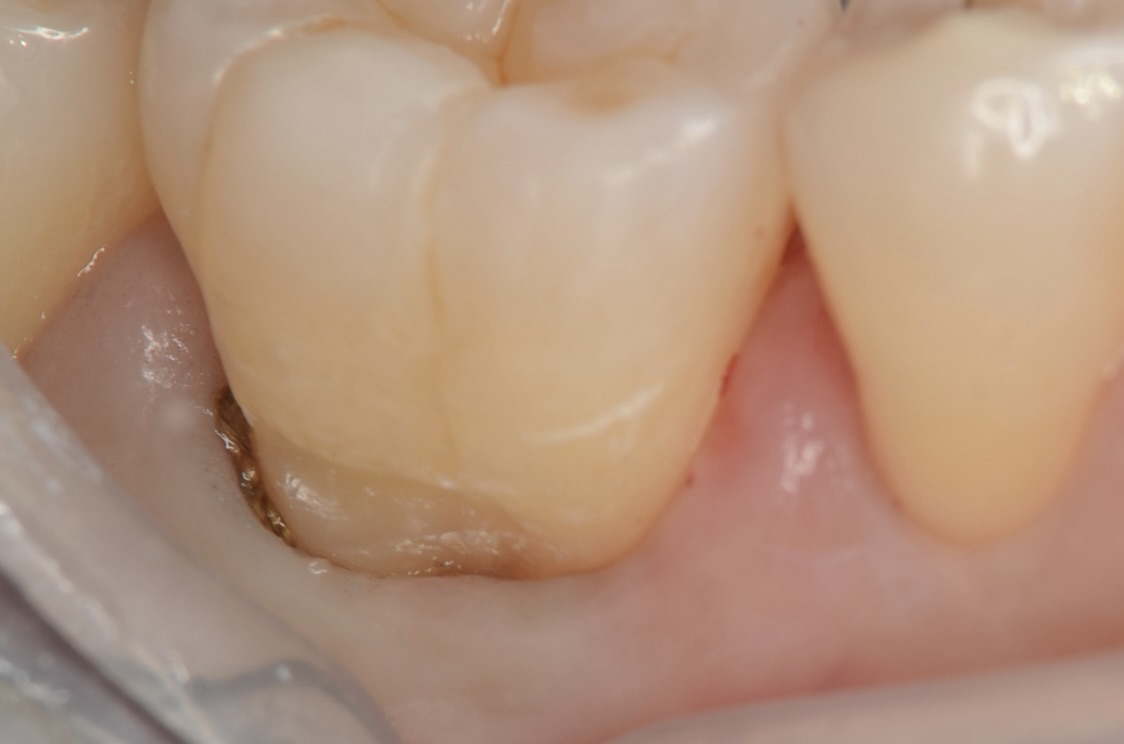

歯頸部齲蝕除去後、歯肉圧排

歯と歯茎の間に細い糸を入れて隙間を意図的に作ります。 -

レジン充填・研磨後

ツルツルに段差なく仕上げました。これで歯垢がつきにくくなります。仕上げにこだわるかどうかで、長持ちするかどうかも決まります。